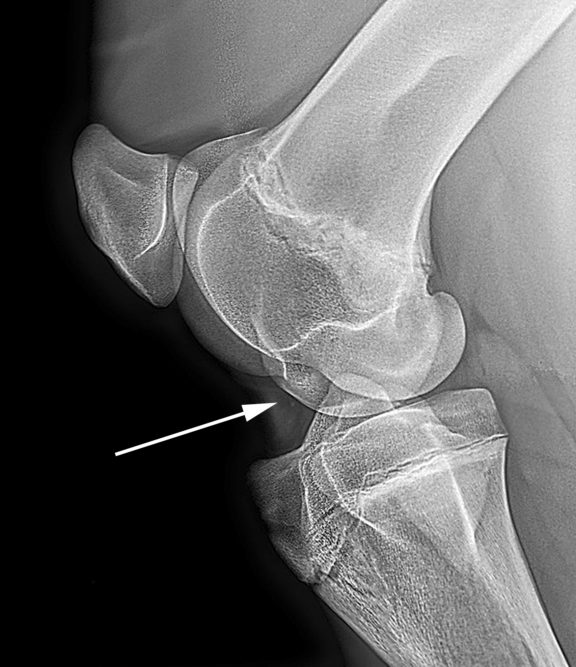

See figure 7 below.